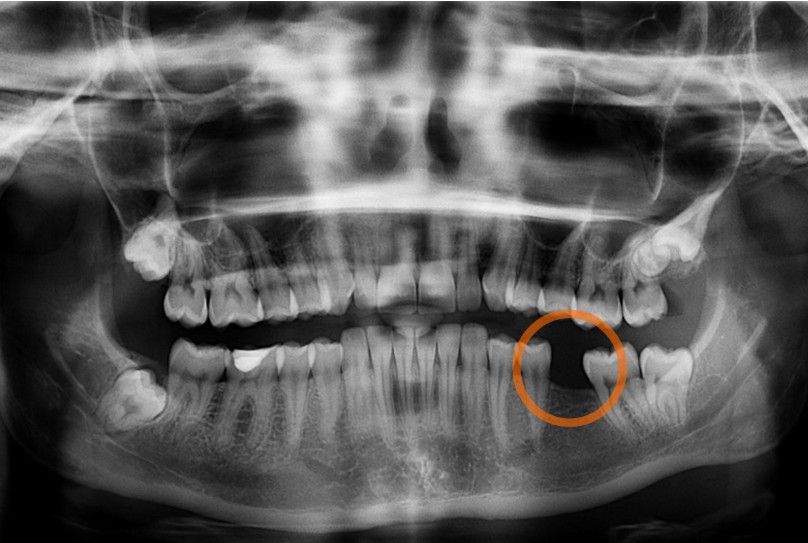

Trồng răng Implant không thể dựa trên thăm khám bằng mắt thường. Chẩn đoán hình ảnh là nền tảng bắt buộc để bác sĩ xây dựng kế hoạch điều trị chính xác và an toàn.

1. Chụp X-quang và CT Cone Beam 3D toàn hàm

Người bệnh cần được chụp phim toàn cảnh (Panorex) và đặc biệt là CT Cone Beam 3D. Phim CT 3D cho phép bác sĩ quan sát cấu trúc xương hàm theo không gian ba chiều, đánh giá chính xác:

Danh sách nội dung bắt buộc phải khảo sát trên phim CT:

– Chiều cao và bề rộng xương tại vị trí mất răng

– Mật độ xương (D1 – D4)

– Vị trí xoang hàm trên

– Đường đi của ống thần kinh răng dưới

– Khoảng cách tới răng kế cận

– Hình thái sống hàm và độ nghiêng xương

Theo các thống kê lâm sàng trong Implant nha khoa, việc lập kế hoạch dựa trên CT Cone Beam giúp giảm trên 60–70% nguy cơ đặt sai vị trí trụ, hạn chế các biến chứng như xuyên xoang, chạm thần kinh hoặc thủng bản xương.